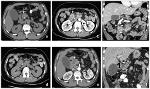

影像学CT与MRI及其新技术新装置在颅内血管性病变诊治中的系列应用研究

徐州德康中汇医疗科技有限公司